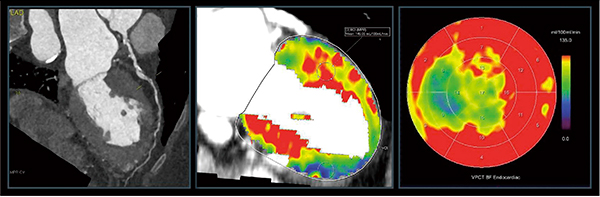

また,SOMATOM Forceでは撮影範囲が110mmに拡大されており,簡便に心筋全体をとらえることが可能となっている(図4)。加えて,高出力のX線管であるVECTRONにより70kVpを用いたダイナミック負荷心筋パフュージョン検査が可能となっており,3〜5mSv程度まで被ばくを低減することできる。低電圧撮影で問題となる電気ノイズに関しては,検出器のアナログ回路を排除したフルデジタルの検出器である「Stellar InfinityDetector」を採用しており,低電圧撮影によるコントラスト上昇を有効に活用することができる。

図4 SOMATOM Forceによるダイナミック負荷心筋パフュージョン

ダイナミック負荷心筋パフュージョンにより,冠動脈CTで描出された左前下行枝の病変に一致して中隔領域の血流が低下していることが示された。

(画像ご提供:オランダ・Erasmus University Medical Center様)